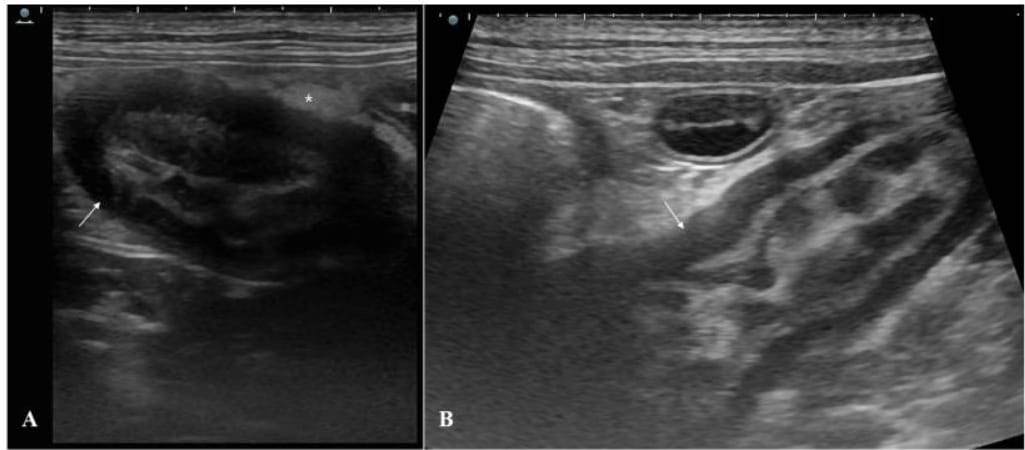

Abdominal ultrasonography of the ileum revealed thickened walls. Diffuse wall thickening and muscular layer hypertrophy ((A,B): arrows) were observed in the distal ileum adjacent to the ileocecal junction. Hyperechoic changes ((A): asterisk) in the surrounding mesenteric fat were also observed.

Ultrasound and capsule endoscopy revealed marked muscular layer thickening and a partially obstructive lesion in the distal ileum. Histopathology confirmed smooth muscle hyperplasia with no mucosal invasion, no neoplastic features, and only mild inflammatory infiltration of macrophages, neutrophils, and lymphocytes. The lesion was classified as idiopathic. Over one year of follow-up, the dog showed significant clinical improvement with increased body weight and only occasional diarrhea. Mild residual muscular thickening persisted on imaging.

A 3-year-old female French Bulldog with chronic diarrhea, vomiting, hyporexia, and weight loss underwent a diagnostic workup including blood tests, abdominal ultrasonography, and capsule endoscopy. These revealed ileal wall thickening with muscular hypertrophy and partial luminal obstruction. Differential diagnoses included neoplasia and chronic inflammatory conditions. Surgical resection and anastomosis were performed from the distal ileum to the ileocecal junction, including full-thickness biopsies for histopathology. Postoperatively, the dog received anti-inflammatory medication (prednisolone), antibiotics (tylosin), and dietary management.